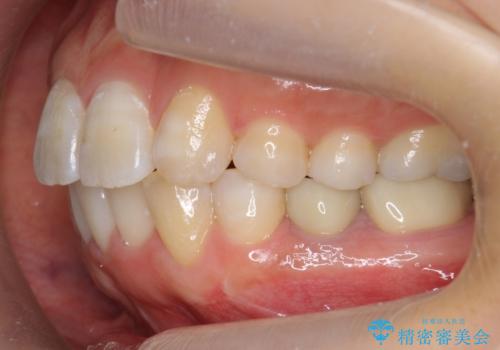

歯のがたつき インビザラインで矯正

- 歯並びを主訴に来院。

左上2番は以前抜歯したとのこと。

奥歯を後ろに下げて、前歯を並べています。

マウスピースと矯正用のミニスクリューを使用して治療しています。